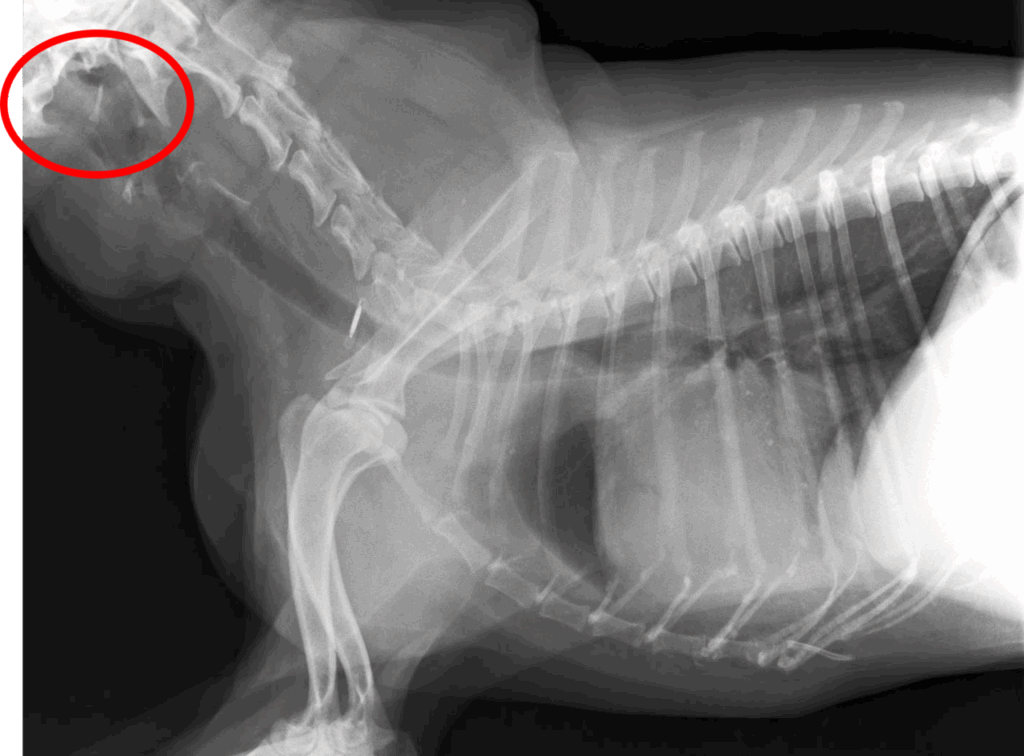

• 胸部レントゲン検査(図1)

肺や胸部の異常はみられませんでした。

これらのことから心不全や肺疾患ではなく、上部気道閉塞が呼吸器症状の原因であると考えました。